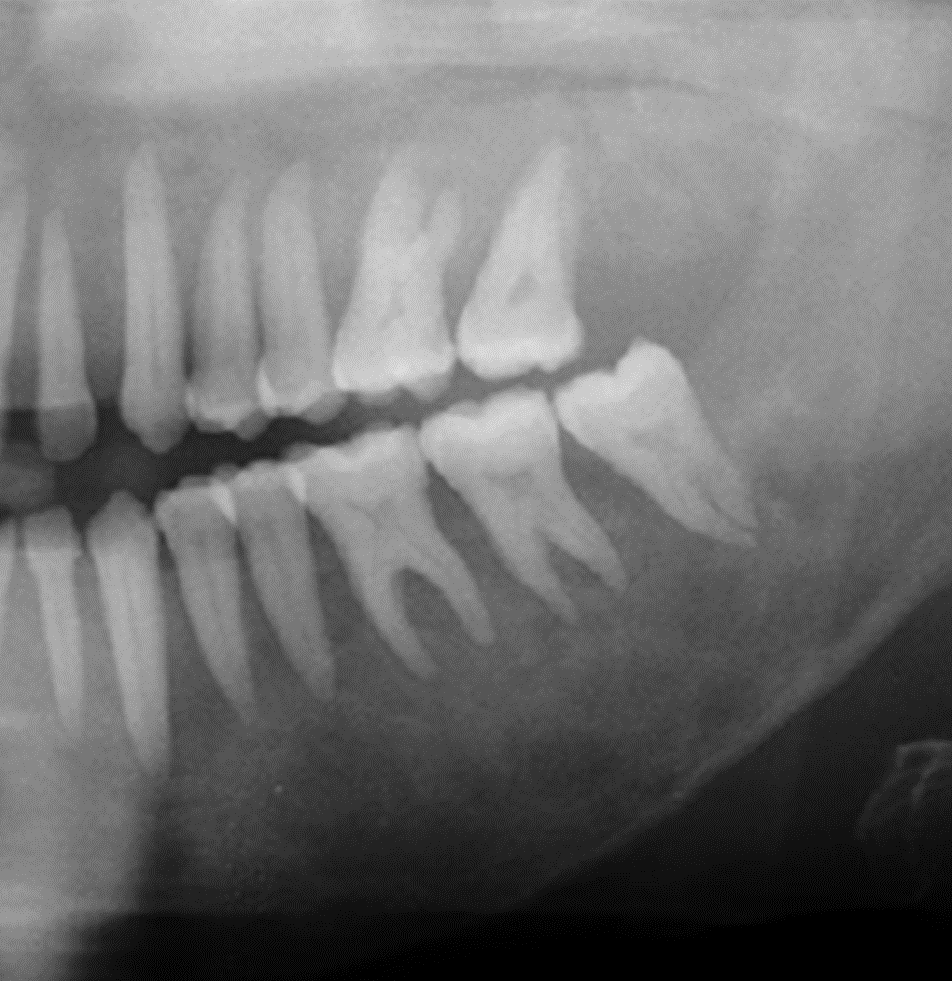

- CP:最近假牙及附近牙齒鬆動的很明顯。

- 平常很注意口腔衛生,尤其在更換新的假牙更注重牙周清潔。

- 口腔檢查確實牙周很好,但是牙齒確鬆動。

- X-光檢查發現牙周的齒槽骨有變化,牙根周圍的lamina dura 明顯的消失。

- 牙周乾淨 → not local cause

- lamina dura missing → 低血鈣 → Hyperparathyroidism